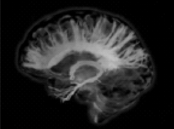

Dice el diccionario de la R.A.E. que la felicidad es un estado de grata satisfacción espiritual y física pero, un poco después, reconoce que para que esto ocurra, también debería darse una ausencia de inconvenientes o tropiezo: algo poco probable en la vida que, por definición, se desarrolla en un entorno cambiante. Sin embargo, incluso socialmente, parece que se está obligado “a ser feliz”… El problema es que esta imposición de la felicidad dificulta el gestionar adecuadamente las emociones llamadas “negativas”... ¡Y el cerebro necesita ambas cosas! Las emociones como la tristeza, el miedo o la ira no son “negativas”, sino necesarias y cargadas de enormes ventajas adaptativas. Vamos a ver por qué.

¿Qué sucede cuando un individuo se desplaza de su “zona de confort”? Que su cerebro explorador inicia todos los mecanismos necesarios para afrontar los cambios. Así, la amígdala dirige el control emocional de sus acciones, mientras el hipocampo limita su alcance basándose en las experiencias previas fijadas en su memoria. El cerebro entonces puede enfrentarse al miedo y alerta, emociones que garantizan su integridad. O puede tener que negociar con un posible desencanto por una experiencia desagradable: empieza así el necesario duelo que le permitirá re-evaluar su situación. Por último, incluso se puede desarrollar un potente enfado que le hará luchar contra lo que es peligroso o injusto.

Pero, obviamente, estas situaciones de alarma no se deben prolongar eternamente. Por ello, nuestro cerebro, a continuación, inicia, también, una serie de mecanismos atenuadores de ese desagradable conjunto de sensaciones. Estas respuestas “de recuperación” son en muchos casos iniciadas por señales químicas como, por ejemplo, la liberación de oxitocina que comunica una sensación de confianza en el entorno.